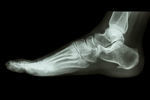

足底筋膜炎

【症例】足底筋膜炎

足底筋膜炎の痛みが長引くと、神経細胞に変化が起こります。

繰返される足裏の痛みを学習し、些細な刺激でも即座に反応する神経に変貌してしまします。

この様な変化を「神経の可塑化」と言います。

神経細胞の可塑化は違和感を痛みと感じてしまったり、小さな刺激でも強い痛みと感じるなど、足底筋膜炎の慢性化、重症化を推し進めます。